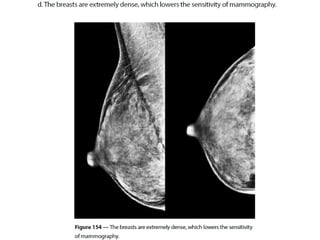

• 1.

Breast imaging basedon ACR2013 MD .Dr.k.sharifi.radiologist